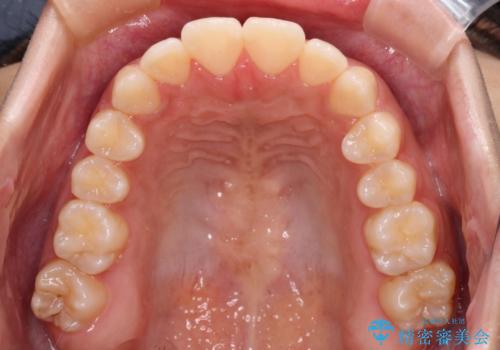

- 上下のデコボコと奥歯の咬みにくさを気にして来院された患者様です。

上顎骨の幅が下顎骨よりも小さく受け口傾向であったため、拡大装置により上顎骨の骨幅を広げて上下関係を改善し、その後インビザラインにて歯並びを整えることとしました。

下顎歯列は上顎歯列内に収まるように並んでいますが、上顎骨の幅が狭いと、下顎臼歯が全体的に舌側に傾斜した歯列となってしまいます。

舌側に傾斜した歯列は奥歯に力の負担がかかりやすく、歯磨きがしにくいなどの問題があるため、上顎骨拡大により舌側傾斜を改善することが可能となります。